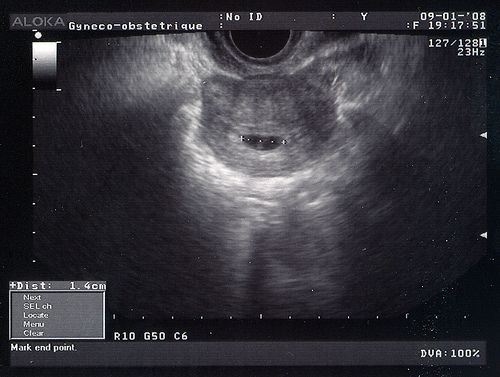

Tu as déjà bien grandi! Le sac est passé de 4 à 14 mm en une semaine. Toi, tu mesures maintenant 2 mm!

Je ne regrette pas d'avoir été te voir, même si c'était à cause de ce foutu stress! Tu ressembles à une virgule un peu plus claire dans le sac foncé.